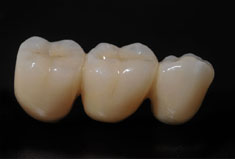

Fehlen in der Front oder im Seitenzahnbereich mehrere Zähne, ist eine Brücke oder Prothese vollkommen unnötig. Die fehlenden Zähne können entweder einzeln durch eine entsprechende Anzahl von Implantaten oder durch implantatgetragene festsitzende Brücken ersetzt werden. Das Bild der Kronen zeigt die drei Verschraubungen deutlich, im Mund liegen diese verdeckt am Gaumen oder im Bereich der Zunge.